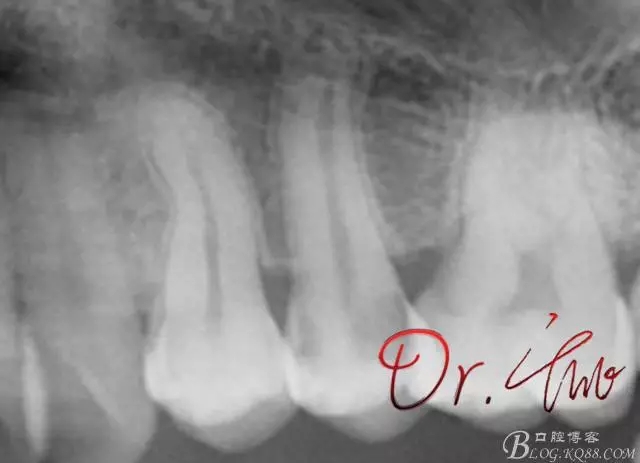

先來第一個病例

初診照

640.webp.jpg